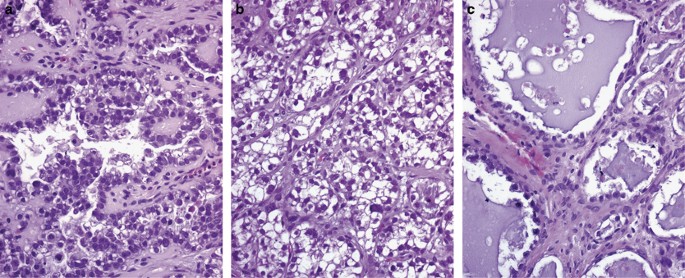

ECa is typically composed of a proliferation of oval or round endometrial glands with a smooth inner contour that are lined by stratified or pseudostratified low columnar epithelium with basophilic, amphophilic, or lightly eosinophilic cytoplasm displaying nuclei that show preservation of their polarity. In addition, a variable amount of solid growth sometimes can be seen filling and distending glandular lumens, which contains cells that bear a resemblance to the cells lining the glands (Figure 1). According to the FIGO grading system, ECa is divided as follows: grade I, up to 5% of solid, non-squamous, component; grade II, 6–50% of solid, non-squamous, component; grade III, >50% of solid, non-squamous, component3 (Figure 2a–c). The FIGO classification also considers that the presence of grade 3 nuclear atypia in the context of an architectural pattern grade I tumor should raise the grade by one;3 however, from a practical standpoint, before making a diagnosis of an ECa, tumors with this feature should raise the possibility of a serous carcinoma glandular variant.